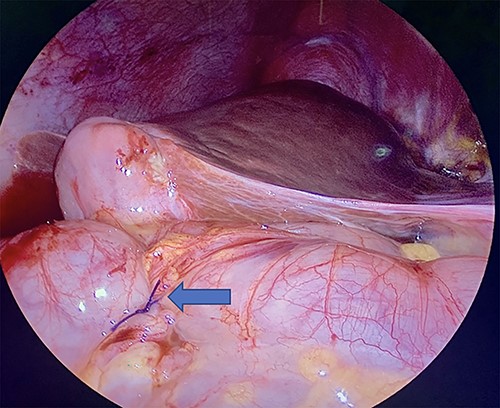

Diagnostic laparoscopy of the abdomen was performed demonstrating diffuse carcinomatosis secondary to known primary gallbladder carcinoma. A portion of the ascending colon was adherent to the abdominal wall and was carefully dissected off. There was no full thickness erosion of the stent, and the stent was palpated through the colon at the ascending colon using bowel graspers. Colonoscopy was next performed, identifying the stent lodged in the mid-ascending colon and another intraluminal portion of the proximal transverse colon that appeared abnormal (Fig. 2A and B). The stent was successfully removed with rat tooth forceps by gastroenterology. The colorectal surgery team then performed two serosal suture repairs on the ascending and transverse colon (Fig. 3).

Laparoscopic visualization of a serosal lembert suture placement on transverse colon (as indicated by arrow; ascending colon serosal repair not featured).